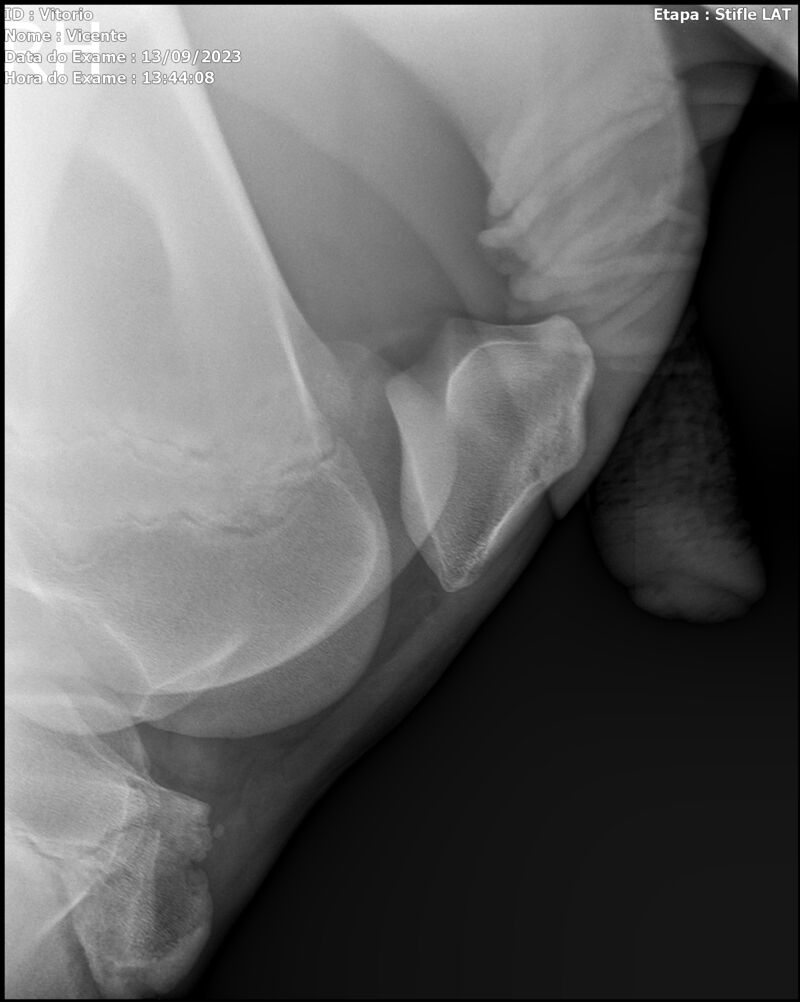

LOTE 13

THUNDER ZC

Raça: BRASILEIRO DE HIPISMO

Sexo: MACHO - POTRO

Nascimento: 17/09/2022

Altura Aproximada: 1,54

Pel.: CASTANHO

Registro: EM AND

Vend.: VICENTE CONTE

Local : PORTO FELIZ/SP